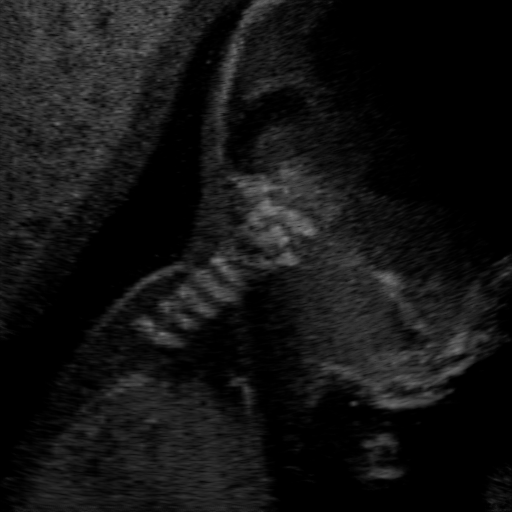

Qualitative Results. Fig. 3 shows a visual comparison of the three model variants on four examples. The baseline L2HM fails to preserve anatomical structures due to missing structural information in the input images. Resulting ambiguities in the network prediction cause artifacts such as blur in regions that feature fine details such as bones. Providing segmentation maps as additional input (L2HMS) greatly reduces such artifacts as shown in Fig. 3(c). However, L2HMS still struggles in modeling complex non-local features such as directional occlusion artifacts, note the lack of acoustic shadows in Fig. 3(c). In contrast, our final model L2HMSA is able to accurately synthesize these features and produces translations significantly closer to the target, as demonstrated in Fig. 3(d). In particular, our proposed model with segmentation and attenuation integral maps is able to recover both missing anatomical structures and directional artefacts.

(a) Input

(b) L2HM

(c) L2HMS

(d) L2HMSA

(e) Target